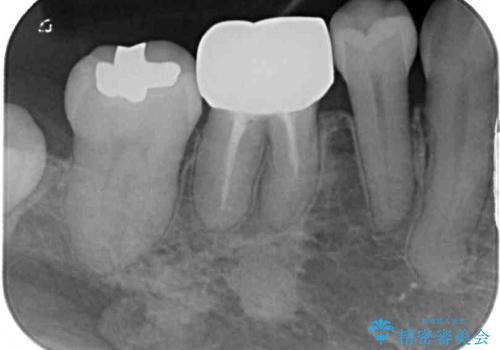

- 矯正治療後に、下顎奥歯の銀歯をすべてゴールドにすることを希望された患者様です。

セラミッククラウンやセラミックインレーによる補綴治療も提案しましたが、お友達にゴールドを自慢したいとのことで、ゴールドクラウンとゴールドインレーにて処置することとしました。

ゴールドは「白い歯」ではありませんが、銀歯の金属色とは異なり、非常にきれいな色合いが特徴です。

もちろん、適合が極めて良いという圧倒的メリットもゴールドクラウンやゴールドインレーの特徴です。